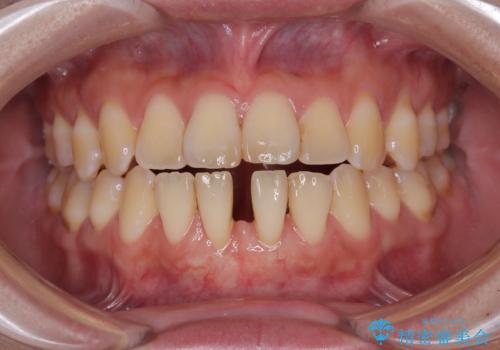

矯正の後戻りによるすきっ歯と歯肉退縮 根面被覆と部分矯正

- 学生時代の矯正治療の後戻りと、それに伴う下顎前歯西肉退縮を気にして来院された患者様です。

舌の突出癖が著しく、それが原因で後戻りと歯肉退縮を起こしている状態でした。

舌のトレーニングをしっかりと行っていくことを前提に、歯肉移植による根面被覆と、部分矯正によるすきっ歯の改善を行うこととしました。

歯肉移植と矯正治療後には非常に満足のいく仕上がりとなりましたが、舌の突出癖は残存しており、今後歯肉退縮とすきっ歯になるリスクを抱えた状態での治療終了となりました。